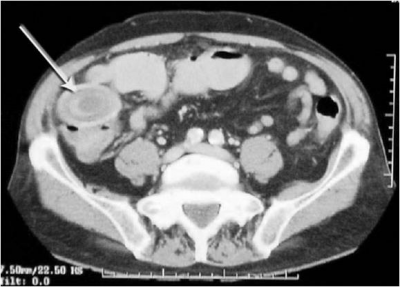

לעתים רחוקות, כדי לקבוע את גובה החסימה ואת מידתה בחולים הלוקים בחסימה דינמית, או כדי להבדיל בין שתי צורות החסימה, יש לצלם את החולה לאחר בליעת חומר ניגוד נספג מסוג גסטרוגרפין. בחסימה דינמית ניתן למצוא התקדמות של חומר הניגוד עד לחסימה (תצלום 6.4), ואילו בחסימה אדינמית ניתן למצוא אמנם מעבר לכל אורך המעי, אך מעבר איטי ביותר. לחולים שבהם יש חשד לחסימת הכרכשת, אין לתת בריום דרך הפה אלא לבצע חוקן בריום תחילה. ב- CT בטן עם חומר ניגוד ניתן לראות לולאות מורחבות שלאחריהן לולאות התמט, בצקת של הלולאות ונוזל ביניהם (תצלום 7.4).

בחולים הלוקים בחסימת מעי על-ידי אבן מרה החודרת למערכת העיכול אפשר להדגים את החסימה בעזרת חומר ניגוד (תצלומים 8.4 ו-9.4) או ב-CT (תצלום 10.4). בחולים הלוקים בחסימת מעי על-ידי פיטובזואר להדגים את החסימה בעזרת חומר ניגוד (תצלום 11.4) או ב-CT. התפשלות של המעי ניתנת להדגמה בצילום בריום או בטומוגרפיה ממוחשבת (CT) (תצלום 12.4 - 13.4)